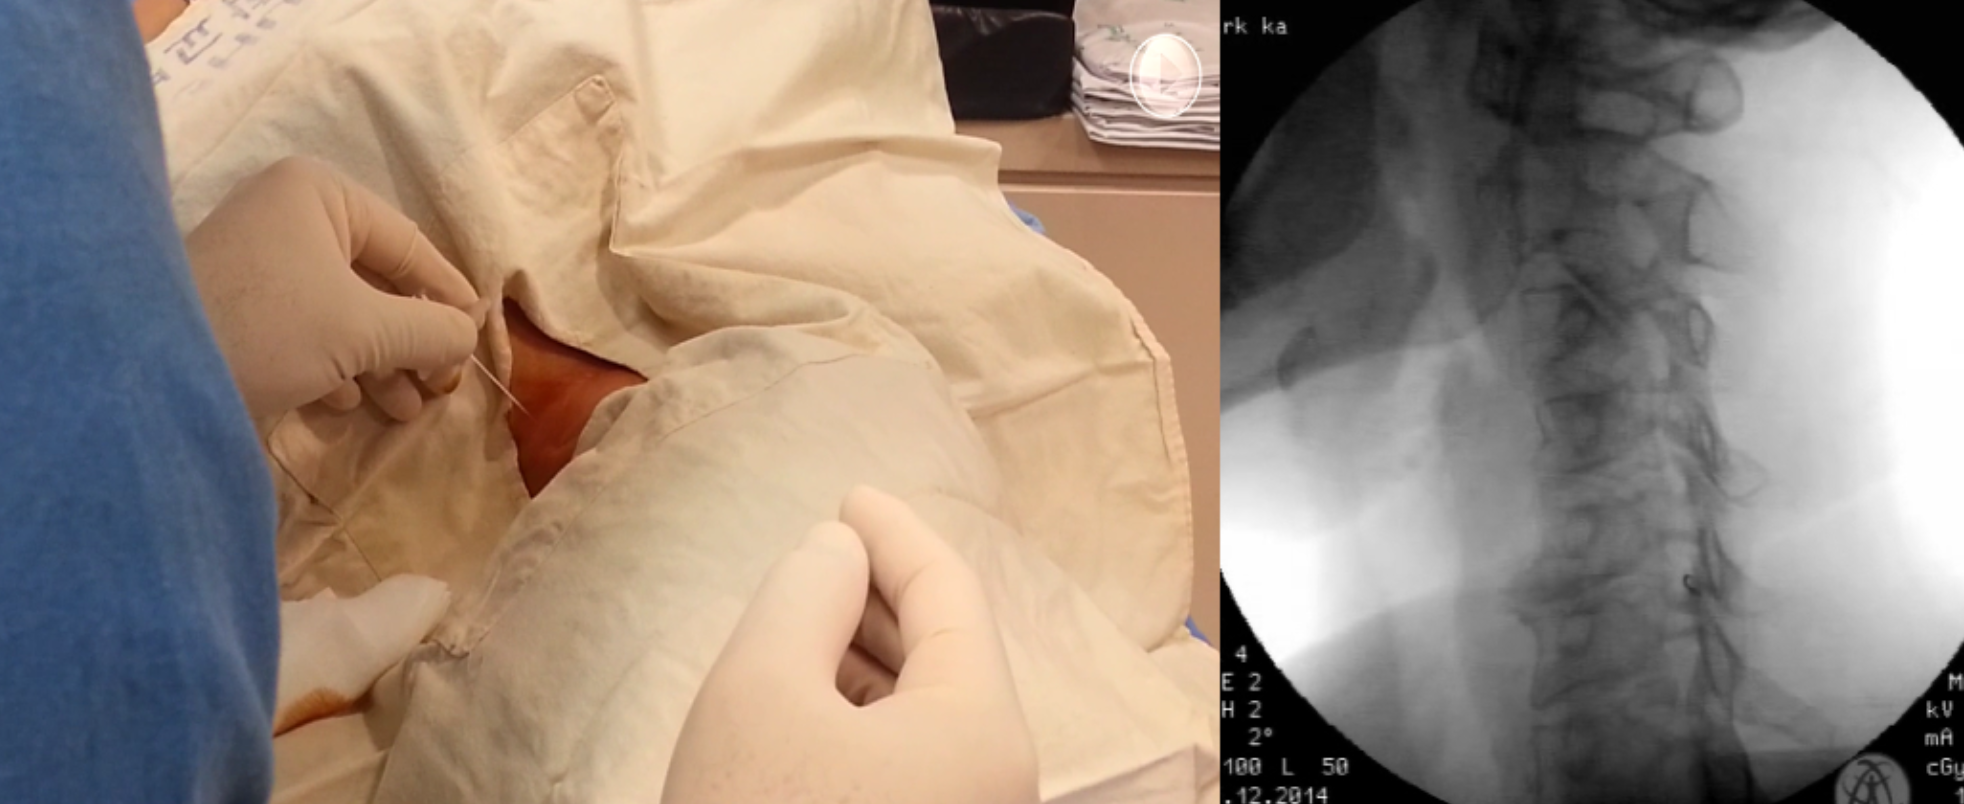

Lumbar TF

Cervical TF

Fluoroscopy guide injection

TFESI

Procedure

- C-arm

- TFESI setting

- S1ย Rotย 15,ย prnย Tiltย Cephย 5~10

- L5ย Rotย 25,ย Tiltย Cephย 5~10

- L4ย Rotย 25,ย Tiltย 0

- L3ย Rotย 25,ย Tiltย Caudย 5~10

- Cย Rotย 45,ย APย Caud 15 (5~10 ๊ฐ๋ถ์ผ์ฑ)